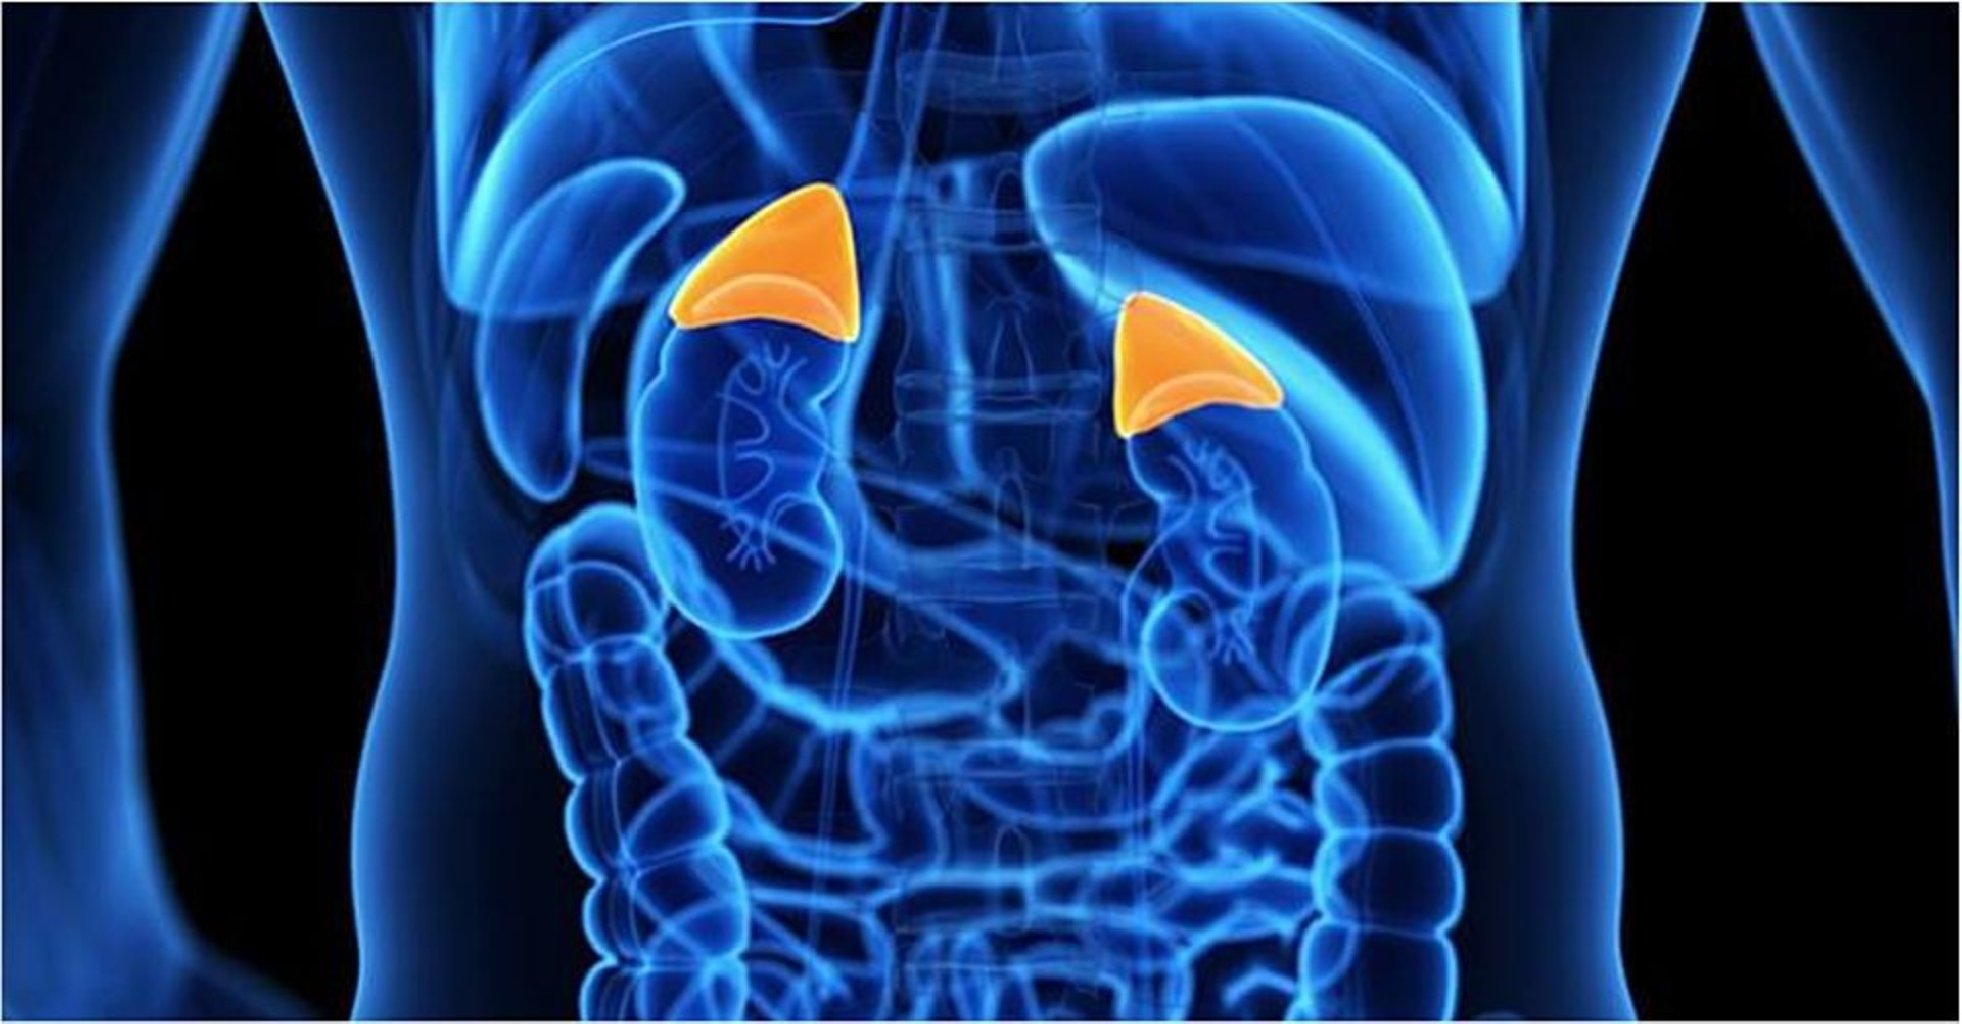

Bir neçə əsas böyrəküstü vəzi xəstəlikləri aşağıdakılardır: Kortizolun artımı və ya Cushing sindr ...

1. Addison Xəstəliyi (Adrenal Çatmazlıq) Addison xəstəliyi kifayət qədər kortikosteroid hormonları ( ...